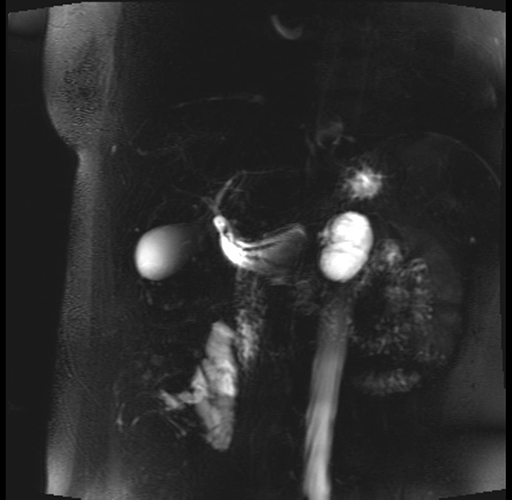

Imaging Analysis

Look through the patient's CT scan to identify any areas of concern for the necessary procedure.

Based on your CT findings, which issue(s) are present and would give reason for "planned slowing down moment(s)" in this case?